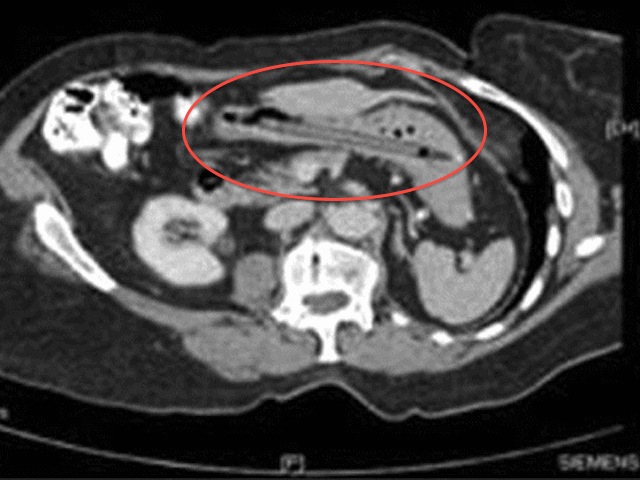

The 76-year-old woman went to an emergency room for diarrhea and unexplained weight loss and a CT-scan found the strange cause, according to the British Medical Journal.

A recent X-ray of the woman’s stomach confirmed her original story. It should also be noted that the pen still writes. Remember that next time your at the gas station or bank. Where has this pen been?

X-ray of the woman’s stomach